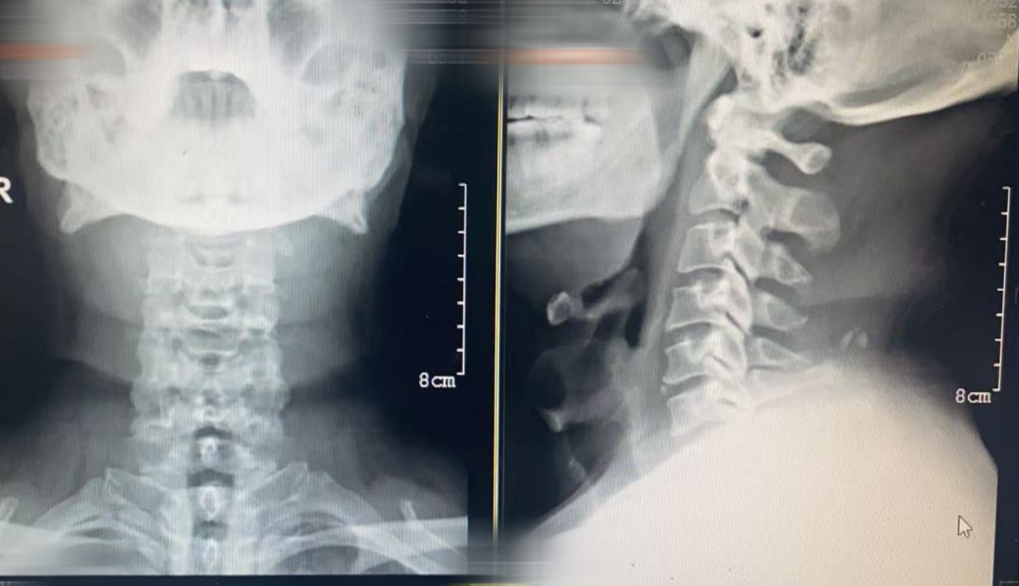

患者基本情况

男性,59岁。

主诉间断颈部疼痛4年,加剧伴双上肢麻木约1.5年。体检颈椎双侧轻微压痛,双侧椎间孔挤压试验阳性,双侧臂丛牵拉试验阳性,其他均正常

专科检查

术前诊断

中医诊断:项痹、血瘀气滞证。

西医诊断:

1. 脊髓型颈椎病

2. 神经根型颈椎

3. 高血压病级2高危

4. 2型糖尿病

5. 一度房室传导阻滞